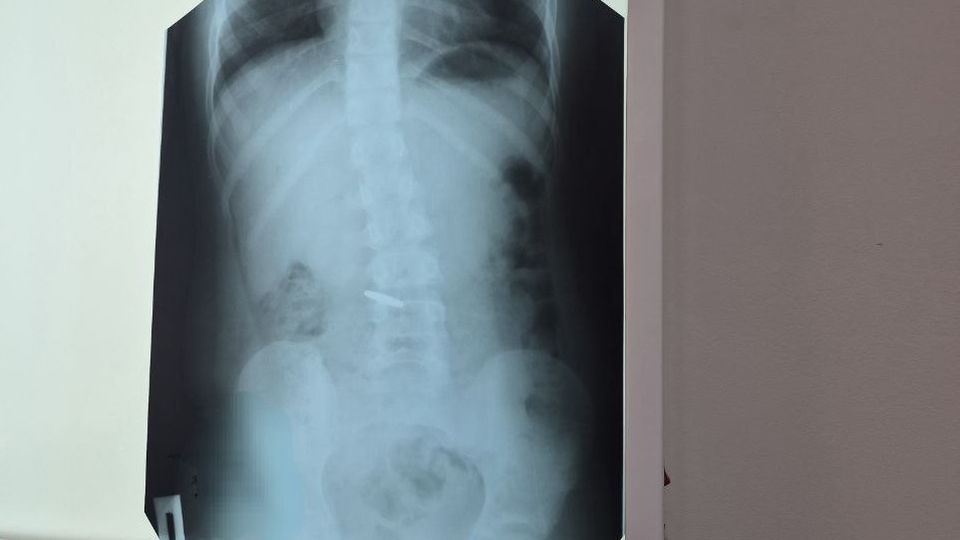

Двое пациентов обратились с проглатыванием инородных тел. В одном случае металлическая монетка вышла естественным путем, во втором – проводилась эзофагогастродуоденоскопия, с помощью которой удалена монета номиналом 10 рублей.